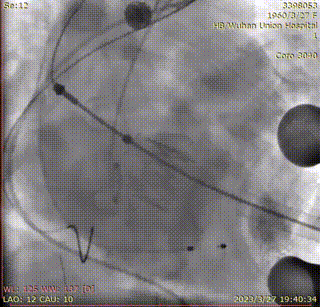

释放瓣膜:

复查根部造影,未见明显反流,瓣膜形态和位置满意,双侧冠脉未见遮挡征象: